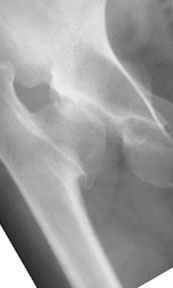

Pic. 1-5 preop plan; 6-8 similar case